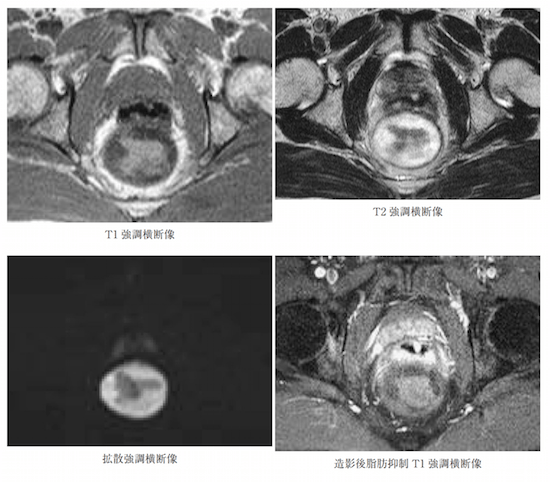

排便時不適的50歲男性脊索瘤患者MRI影像

骶骨前,直腸背側(cè)有腫塊性病變。T2WI為高信號,DWI為高信號。沒有提供ADC。對比中有輕微的對比效果。懷疑脊索瘤的發(fā)現(xiàn)。